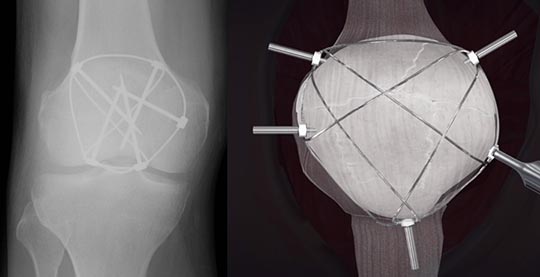

一般に、小さな骨片による骨折が多いので、細い針金や特殊な糸を巻いて固定する方法が良く行われています(図3a, b)。この細い針金や糸を結び付けたり、あるいは、ひまわりの花の様に折れた膝蓋骨の回りを巻いたりすることによって(図4)、膝蓋骨を強く引っ張る力に対抗して、骨折した膝蓋骨が引き裂かれるのを防ぎます。これにより早々に膝の曲げ伸ばしやそのまま歩行することが出来、治療後のリハビリの時間を短縮させる長所を持っています。

図4 ひまわりの花の様に、折れて砕けた膝蓋骨の回りを巻いて固定する方法

(ひまわり法 https://himawari-method.jp)